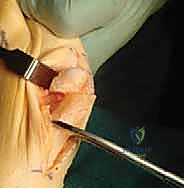

c. Metatarsal Shaft Exposure and Plantar Protection:

With the medial eminence resected, we now need to expose the first metatarsal shaft. We achieve this using sharp subperiosteal dissection. This means we stay directly on the bone, meticulously lifting the periosteum and soft tissues.

This is a critical step, fellows. As we dissect plantarly, we must take extreme care to protect the plantar neck vascular bundle to the metatarsal head. This bundle provides the primary blood supply. Aggressive dissection or careless retraction in this area can lead to avascular necrosis.

Surgical Warning: Always maintain a subperiosteal plane to shield the plantar neurovascular structures. Use gentle, broad retraction.

For proximal plantar exposure, we use a large Langenbeck retractor to gently protect and retract the plantar flap. This allows us to safely visualize the plantar aspect of the metatarsal without disrupting the crucial plantar blood supply. We identify the tarsometatarsal joint proximally, but there's no need to expose it further.